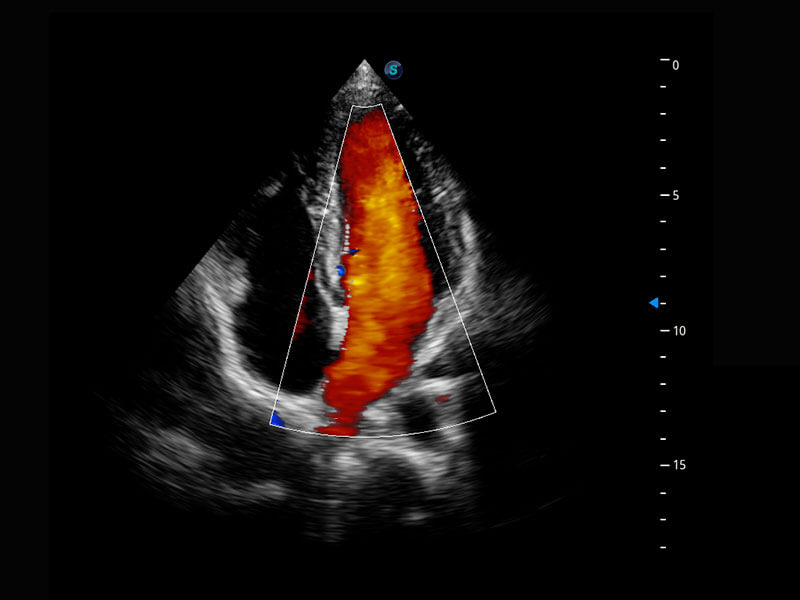

P60搭載一系列胎兒心臟成像技術(shù),實(shí)現(xiàn)精細(xì)的胎兒心臟評(píng)估。

四腔切面

四腔心血流

右室雙出口

胎心容積成像